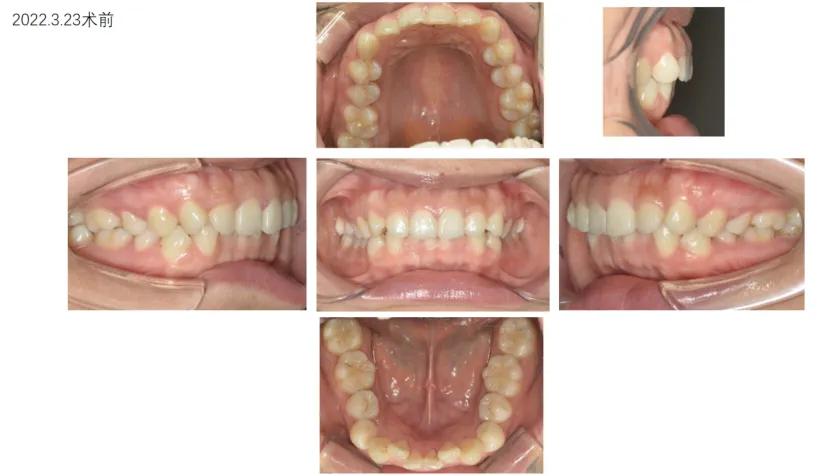

病例展示: